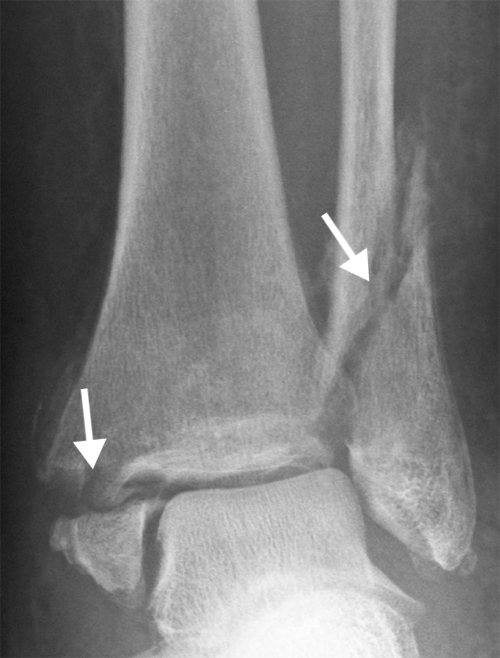

Diagnosen stilles i første omgang basert på fysikalsk undersøkelse og pasientens fortelling. Det brukes såkalte Ottawa ankle rules: dette er retningslinjer som hjelper med å avgjøre om røntgenbilde er nødvendig.

Det vurderes trykksmerter på bestemte punkter, og om pasienten kan gå noen skritt. Ved mistanke om brudd i ankel eller fot er dette vanligvis synlig på røntgen.